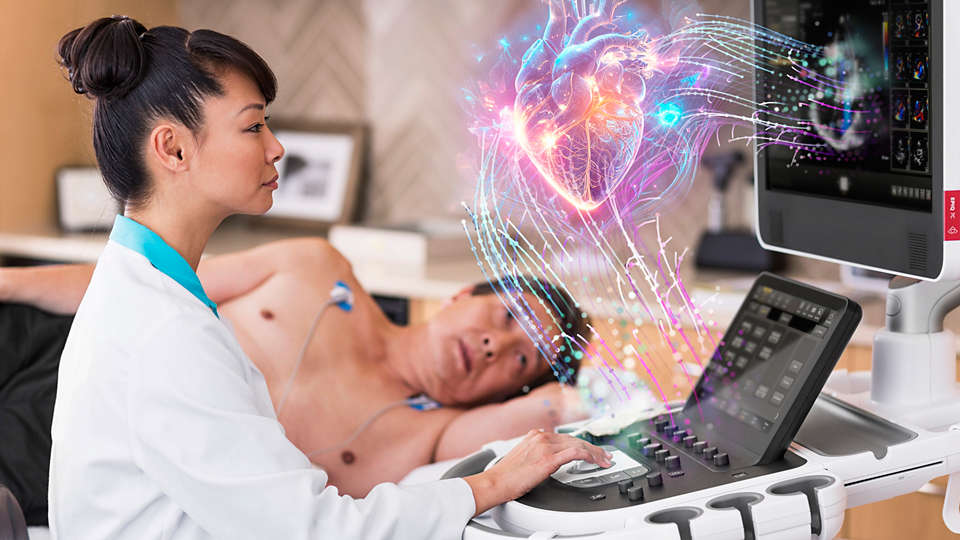

With powerful tools and AI-based technology to help you practice on the leading edge of cardiovascular medicine, EPIQ CVx transcends today’s limitations to advance care for more patients in more ways. It helps ensure consistent image acquisition and interpretation across scans for standardized results for both routine and specialized imaging needs. EPIQ CVx also provides greater automation and collaboration, so you can save time, get real-time input and focus on your patients.

Designed to address the full spectrum of patient exams, Affiniti CVx delivers standardized results as you move across both routine and specialized procedures. Its AI-based technology combines with advanced tools to help you manage clinical complexities, and its efficient automation enhances workflow and reduces tedious tasks.